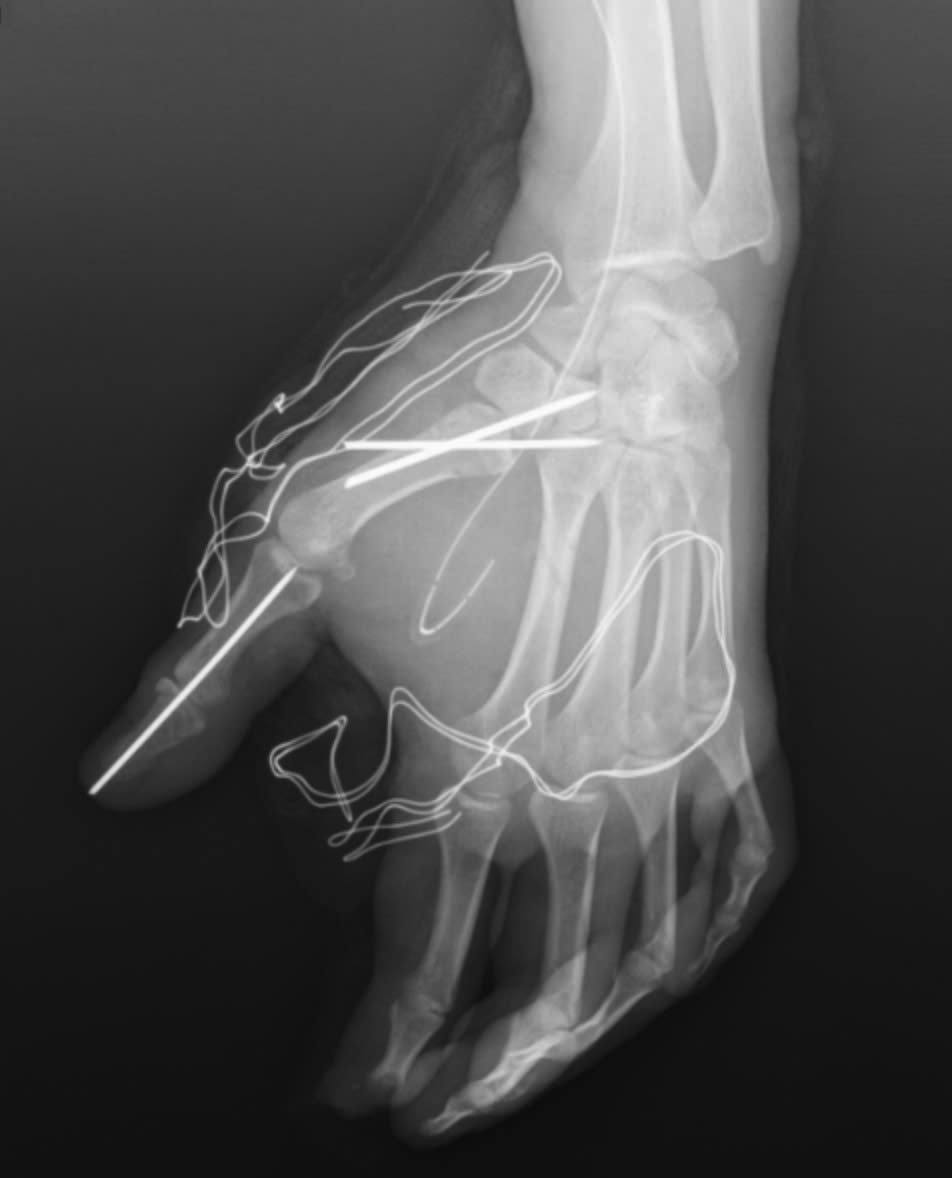

Trong quá trình phẫu thuật, các bác sĩ khoa Phẫu thuật Chấn thương Chỉnh hình và Y học thể thao đã tiến hành cắt lọc tổ chức dập nát, lấy bỏ dị vật trên bàn tay của người bệnh. Đồng thời, vết thương được làm sạch, các cấu trúc gân, thần kinh và mạch máu còn lại được bảo tồn tối đa. Cuối cùng, các bác sĩ cố định xương gãy và khớp bị trật cho người bệnh.

Tai nạn trong tích tắc vì pháo nổ, nam thanh niên suýt mất chức năng bàn tay- Ảnh 3.

Bàn tay nạn nhân bị dập nát sau tai nạn pháo nổ.